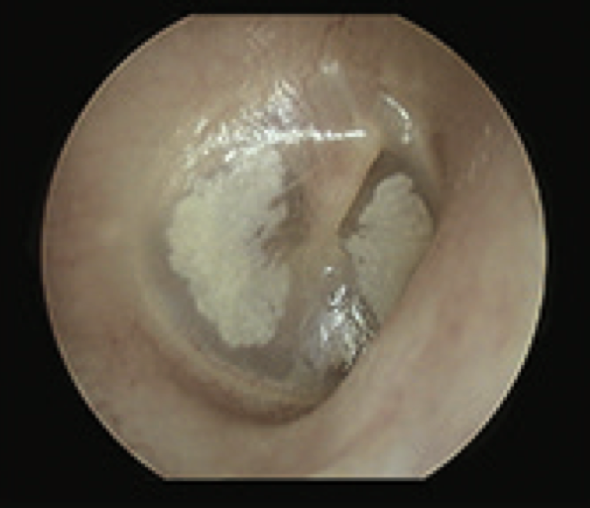

10

Q

What is this?

A

Tympanosclerosis

- intact TM

- deposition of calcium